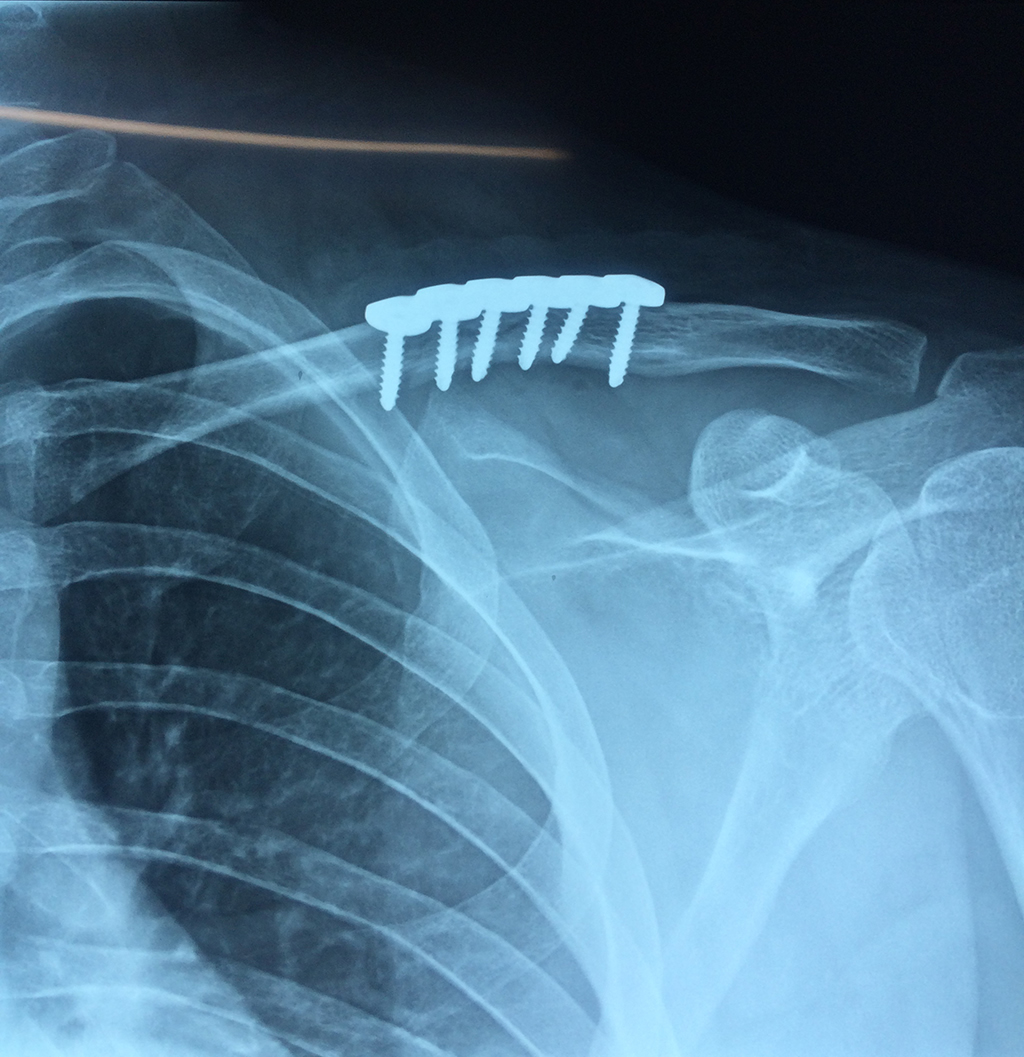

Cirugías de Hombros - Clavícula